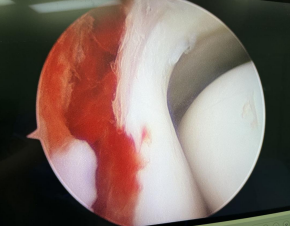

第二天,业务院长石荣剑、曹广超主任、赵亮主治医师手术团队为患儿进行了“关节镜下左踝关节滑膜清理+胫骨骨折复位内固定术”,手术取2个切口,关节镜进入关节腔内,见关节内滑膜增生,部分呈絮样悬浮状,刨刀清理增生滑膜组织。探查见胫骨远端骨折累及前踝、内踝,骨骺分离,骨骺骨折,关节镜监视下,对骨骺予以保护,复位胫骨远端骨折端,螺钉固定断端。手术40分钟顺利结束。

关节镜下